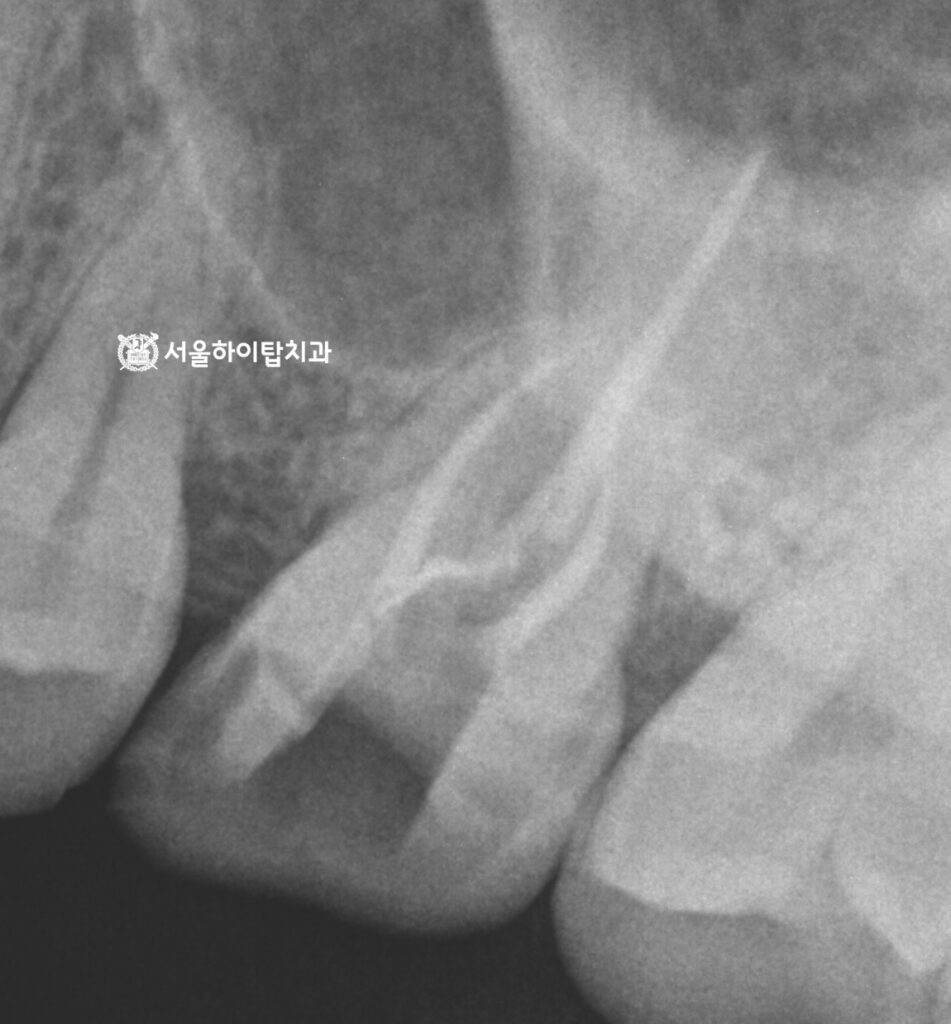

먼저 사진 기준 오른쪽

어금니부터 살펴보겠습니다.

사실 pulpitis은 엑스레이나 PA만으로는

명확히 보이지 않는 경우가 대부분입니다.

동암 치과 에서 그 이유 설명드리자면,

염증이 신경 내부에서 진행되더라도

방사선 사진에는 뚜렷한 변화가

늦게 나타나기 때문입니다.

따라서 뿌리 끝까지 염증이 퍼졌는지,

또는 파절이 동반되었는지를 확인하기 위해|

PA와 환자의 주관적인 증상 평가가 중요합니다.

동암 치과 에서는 다행히 PA로

파절이나 치근단 염증은 보이질 않지만,

이미 저작 시 통증이 느껴지는 상태였기에

치수염이 진행 중임을 알 수 있습니다.

이어서 반대편으로 넘어가면,

치관부 중앙에서 치근단까지 이어지는

명확한 파절선(fracture line)이 관찰됩니다.

이는 단순 균열을 넘어

치근 파절(root fracture) 로

진행된 상태로 볼 수 있습니다.